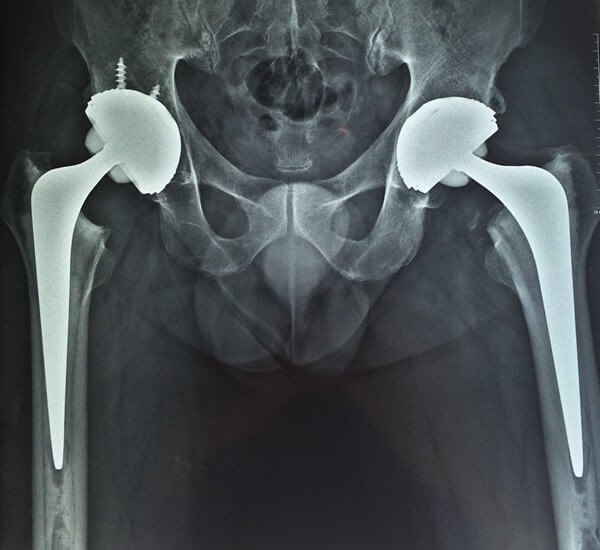

8 Duas próteses híbridas, à direita o acetábulo com parafusos

Fig. 8 - Duas próteses híbridas, à direita o acetábulo com parafusos

Obs.: Os exemplos de radiografias apresentados acima são de pacientes operados por mim e publicados com seu consentimento, preservando sua identidade.